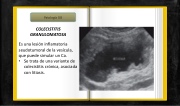

COLECISTITIS GRANULOMATOSA

Es una lesión inflamatoria seudotumoral de la vesícula, que puede simular un Ca.

• Se trata de una variante de

colecistitis crónica, asociada con litiasis.